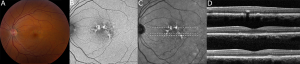

Fundus photography, fundus autofluorescence imaging (FAF), optical coherence tomography (OCT), and near-infrared reflectance imaging (NIR) are useful imaging modalities to establish a diagnosis of PPS maculopathy. Imaging findings are typically symmetric between both eyes, with rare cases of disease asymmetry.[11][12][21]

Color fundus photography typically shows more subtle manifestations compared to FAF. Hyperpigmented macular spots and deep yellowish subretinal deposits may be apparent, particularly in milder cases.[11][12][15][16] Patchy parafoveal RPE atrophy manifests in more advanced cases.[7][11][12][31]

Fundus autofluorescence imaging reveals a striking, densely packed array of hyper- and hypoautofluorescent spots typically centered on and involving the fovea.[4][7][11][12] Hyperautofluorescent spots colocalize with pigmented spots and yellow subretinal deposits apparent on color fundus photography.[7][11][12] In cases where the disease extends to the periapillary region, there is typically a hypoautofluorescent peripapillary halo.[11][12] RPE atrophy may also be noted in more severe cases, initially as multifocal parafoveal lesions, that ultimately coalesce and encroach on the foveal center. Widefield FAF imaging is helpful to elucidate the extent of involved tissue.[11]

Optical coherence tomography shows hyperreflective nodules at the level of the RPE that colocalize with macular pigment clumps on color fundus photography, hyperautofluorescence on FAF, and hyperreflectance on NIR imaging.[7][11][12] Unlike typical drusen or subretinal drusenoid deposits, these lesions appear to reside at the level of the RPE and project a shadow onto the underlying choroid.[11][33] These lesions may not be present on macular OCT in late-stage atrophic disease.[11] Although there may be ill-defined irregularity in the outer retinal bands, there is no clear OCT correlate for yellow macular deposits or the hypoautofluorescent component of FAF lesions.[11][12] OCT angiography may be demonstrate choriocapillaris flow deficits, which may precede other imaging abnormalities in individuals with high PPS exposure.[13][14]

Age-related macular degeneration can be differentiated most readily by looking for the characteristic pattern of PPS maculopathy on FAF imaging, as described above.[33] Additionally, the hyperreflectant RPE lesions observed in earlier stages of PPS maculopathy are distinct from drusen and subretinal drusenoid deposits of AMD. In PPS maculopathy, these lesions appear to be at the level of the RPE and project a shadow onto the underlying choroid, and colocalize with highly hyperreflectant lesions on NIR imaging.[33] In one study comparing PPS maculopathy to AMD, there were no typical macular drusen in eyes with PPS maculopathy.[33] In patients found to have PPS maculopathy, there was a significantly greater likelihood of having pigment clumps at the level of the RPE as compared to AMD.[33]